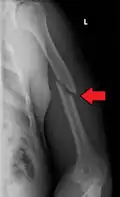

A transverse fracture of the humerus shaft -